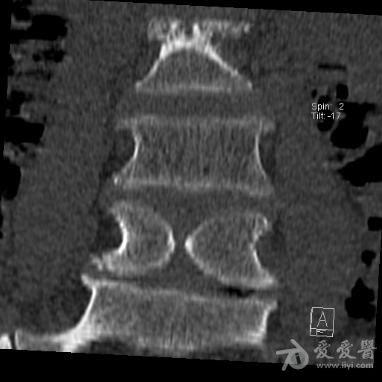

蝴蝶椎(ct)

图片尺寸382x382